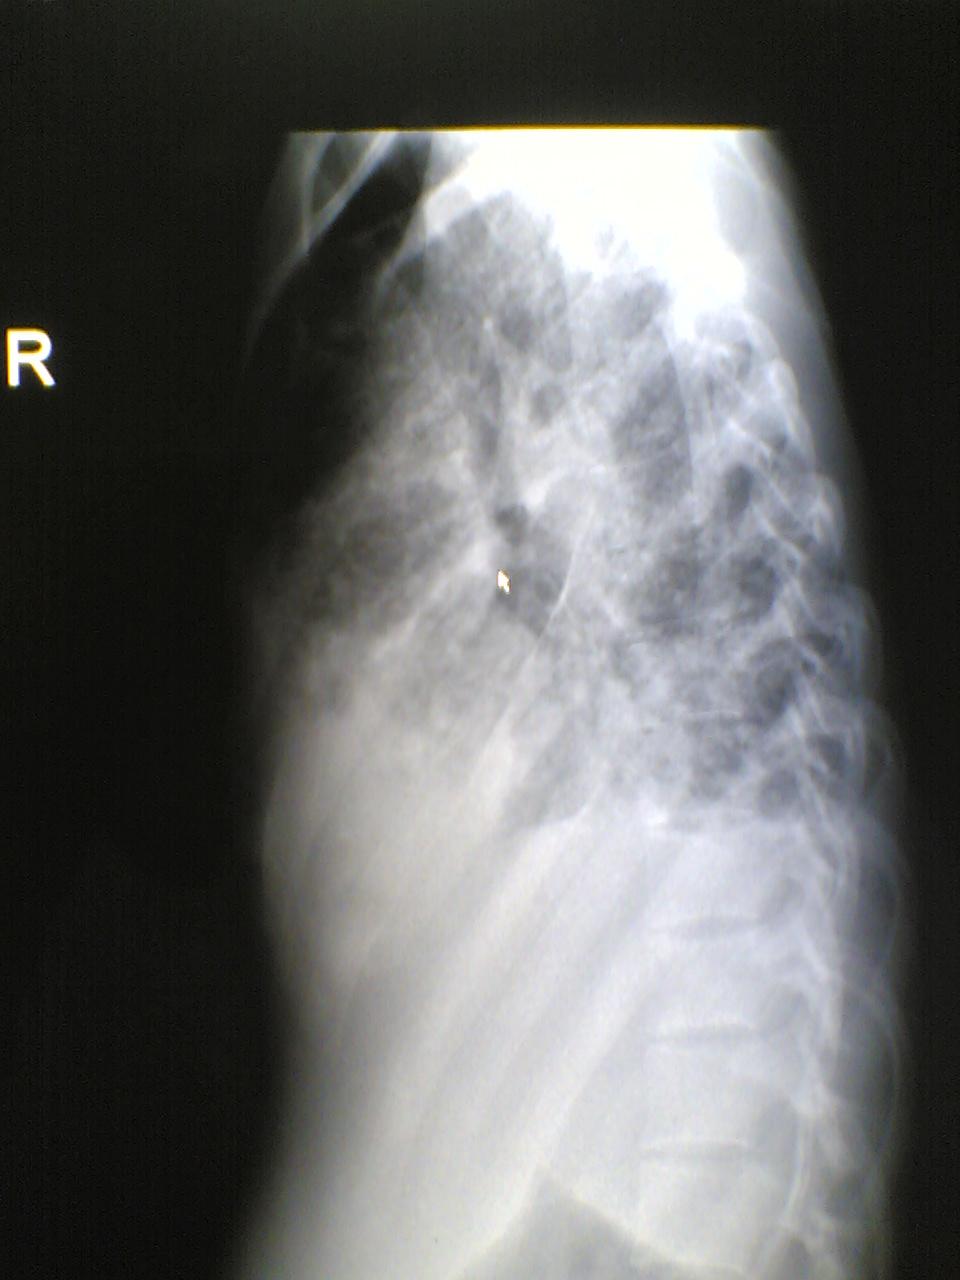

标题: X7068:女,25岁,自觉胸部气紧不适一年。请老师指教。

左肺结核病灶?肺泡癌?

病人年轻,病史较长1年,还是考虑慢性病 结核了, 侧位看上肺也有片絮状病变,当然要做个ct ,估计右侧为实变和胸腔积液